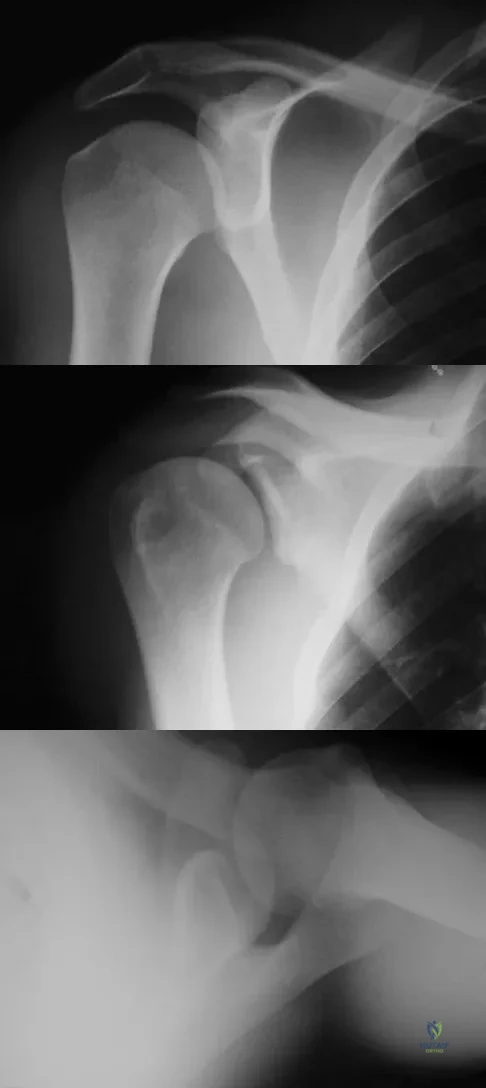

Question 28

A 21-year-old right hand-dominant male collegiate swimmer reports painful clicking in the right shoulder. He states that he can occasionally feel his shoulder "slip out" when he is working out. AP, true AP, and axillary radiographs are shown in Figures 39a through 39c. What is the next most appropriate step in management?

Explanation

Question 30

A 72-year-old woman who was doing well after undergoing total shoulder arthroplasty for arthritis 4 months ago is suddenly unable to elevate her arm. Examination reveals 70 degrees of external rotation compared with 45 degrees on the uninvolved side, and she is unable to lift her hand off her lower back. Radiographs are shown in Figures 43a through 43c. Treatment should consist of

Explanation

Question 98

A 25-year-old man underwent a Putti-Platt repair for recurrent anterior dislocation of his right shoulder 9 months ago. He reports no further episodes of instability but continues to have severely restricted motion, with external rotation limited to less than 0 degrees with the arm at the side. He has pain at the ends of range of motion and restricted activities of daily living despite undergoing nearly 9 months of physical therapy. Radiographs of the shoulder show no arthritic changes. Management should now consist of

Explanation